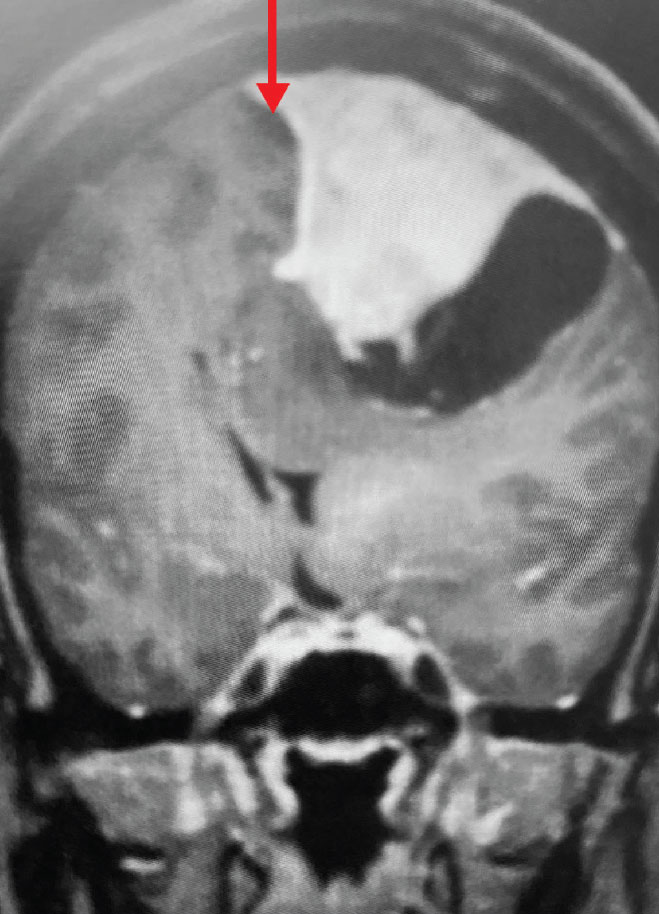

Fig 2. B) Post-operative, post-contrast, coronal MRI.

Treatment: Given the size and location of this tumor, the best treatment was surgical removal. Surgery was performed by Dr. Michael Brisman. A craniotomy exposed the tumor along the convexity as well as the superior sagittal sinus. The tumor was removed, as was the involved convexity dura and the affected segment of the sagittal sinus. Removed dura and skull were replaced with duraplasty (with artificial dura) and a titanium mesh cranioplasty.

Outcome: The patient did very well and made a full recovery.